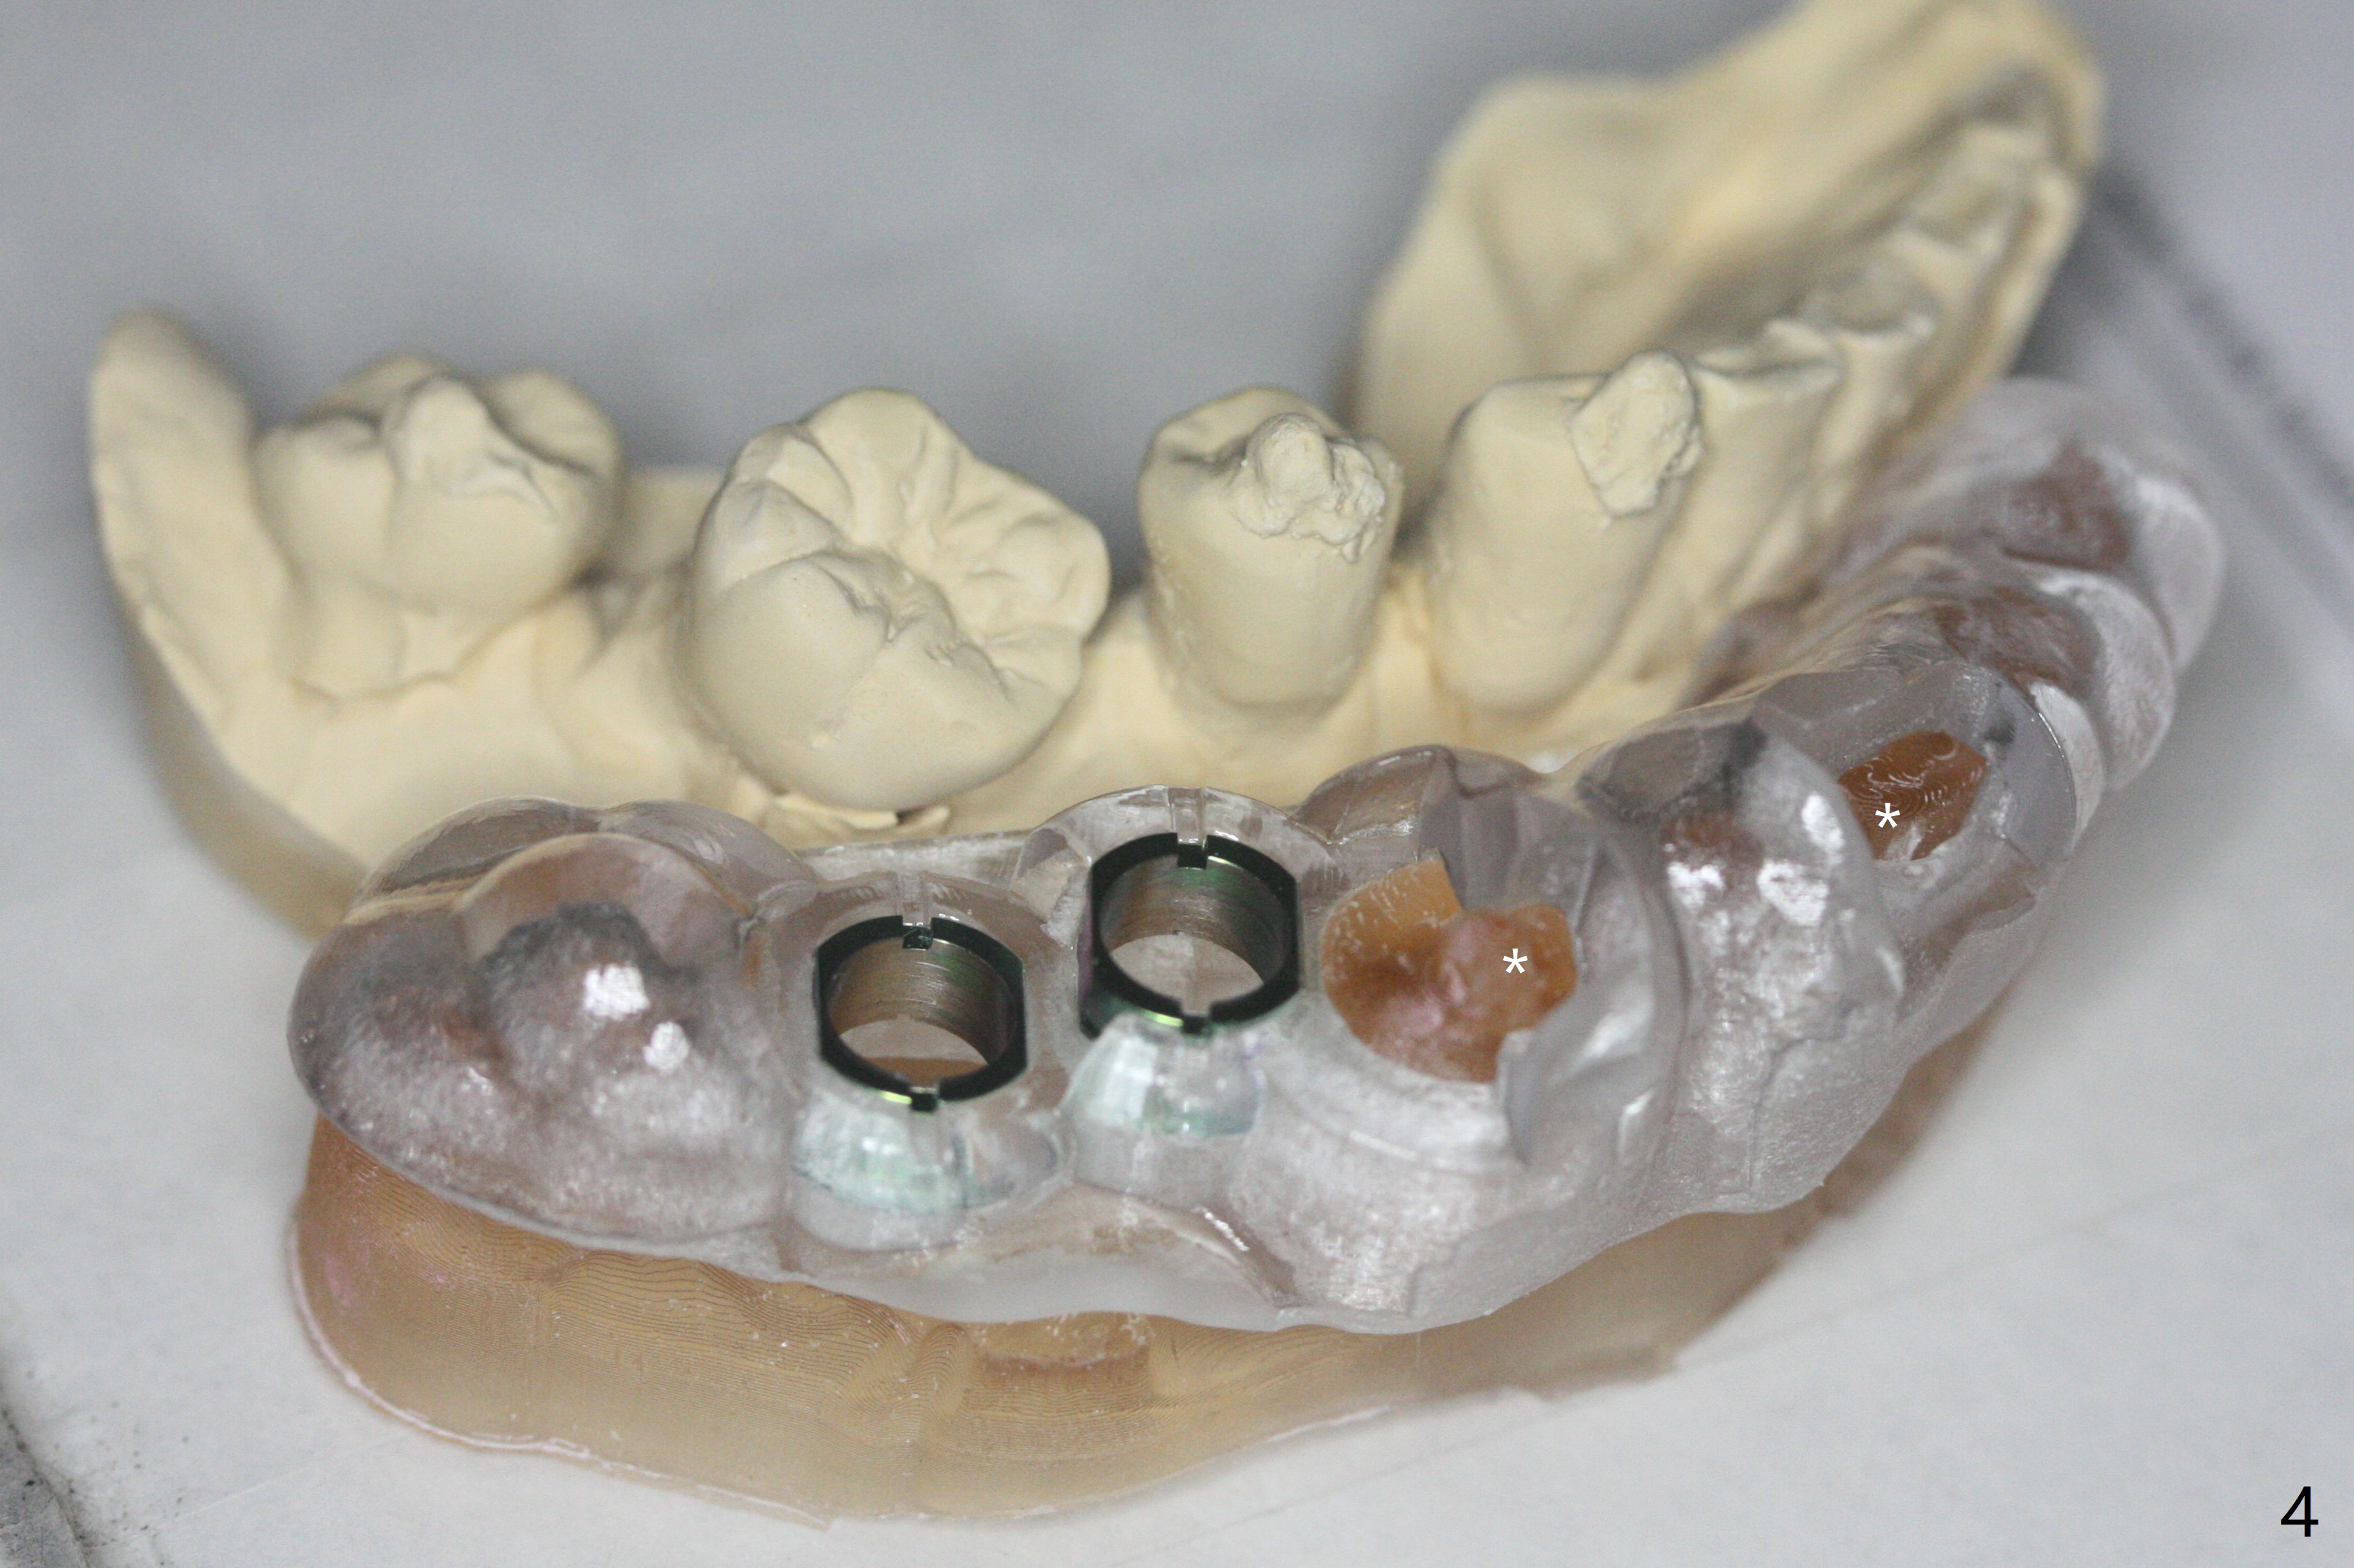

64岁男4年前完成右下7种植,局部矫正病人半途而退(图一),最近6不能保留,准备拔除6;5,6种植。为了减少射线干扰,在3,4(no bonding),7咬合面放置树脂标记(图二:*),先拍摄CT(图三),然后取模或者口腔扫描,DICOM, STL文件/图像就可以融合,制作准确导板(图四)。5,6金属圈不在一个平面,前者有利于钻洞准确,后者有利于钻头进入,常用于第二磨牙,张口度有限时。